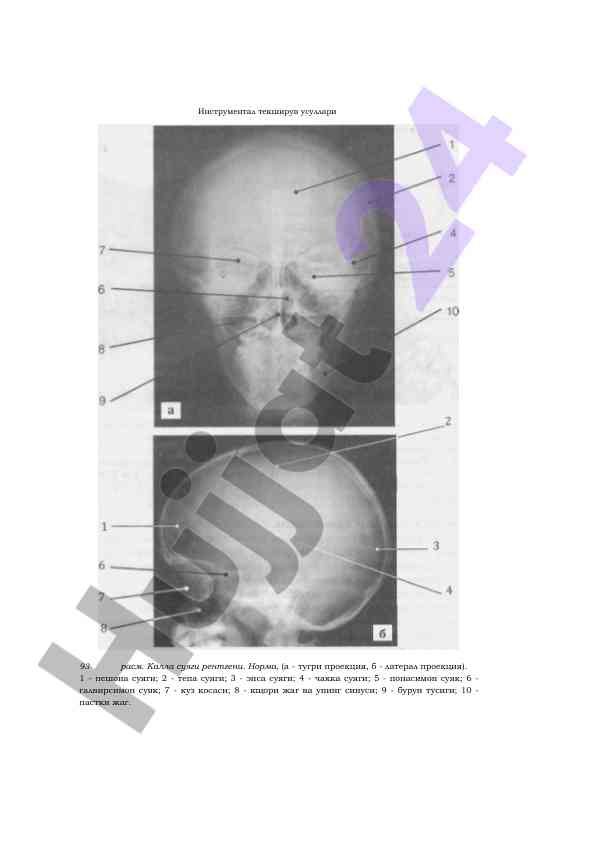

Rengtenologik tekshiruvlar neurodiagnostikada muhim ahamiyatga ega. Ushbu maqola rengen tekshiruvlarining tibbiyotdagi o'rni va usullarini o'rganadi.